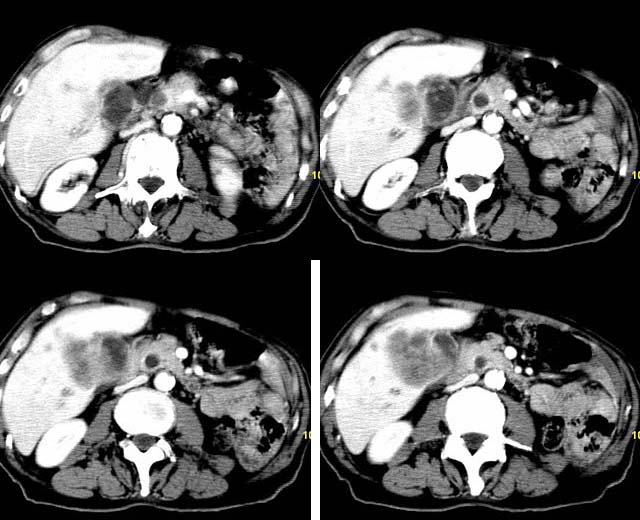

以下是引用余辉在2007-12-6 22:23:00的发言:[br]胆囊内多枚结石影,胆管全程扩张,右肝内病灶强化符合脓肿表现现(左肝病灶图像未传完),考虑急性梗阻性化脓性胆囊胆管炎合并肝多发脓肿(建议补传左肝病灶图像)